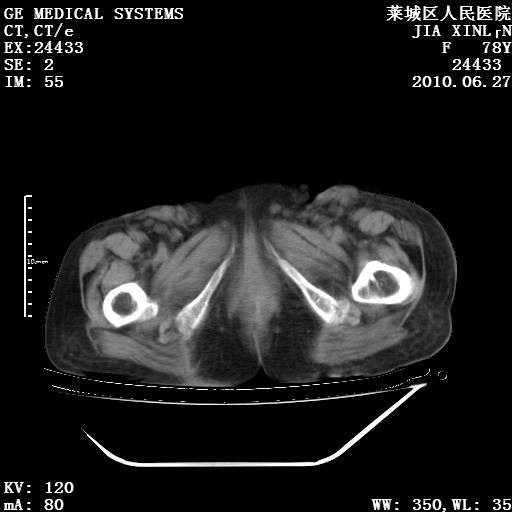

以下是引用胡宇在2010-7-2 19:11:00的发言:[br]神经纤维瘤的特点为:肿块呈多发性、数目不定,少的几个,多的可成百上千难以计数。小的如米粒,大的似拳头,甚至可达十数公斤以上。可松弛地悬挂于皮表,皱褶及松弛可致畸形明显。神经纤维瘤沿神经干的走向生长时呈念珠状,或蚯蚓块状形结节。此外神经纤维瘤皮肤可出现咖啡斑,大小不一,形如雀斑小点状,或大片状,分布与神经纤维瘤肿块的分布无关。肿瘤数目不多的患者,皮肤色素咖啡斑状沉着是纤维神经瘤的重要诊断之一。 本病多发于躯干,有时出现于四肢及面部,患者常合并许多疾病应予重视加以区别。 [br] [br] [br] [br]lyb999说 [br]